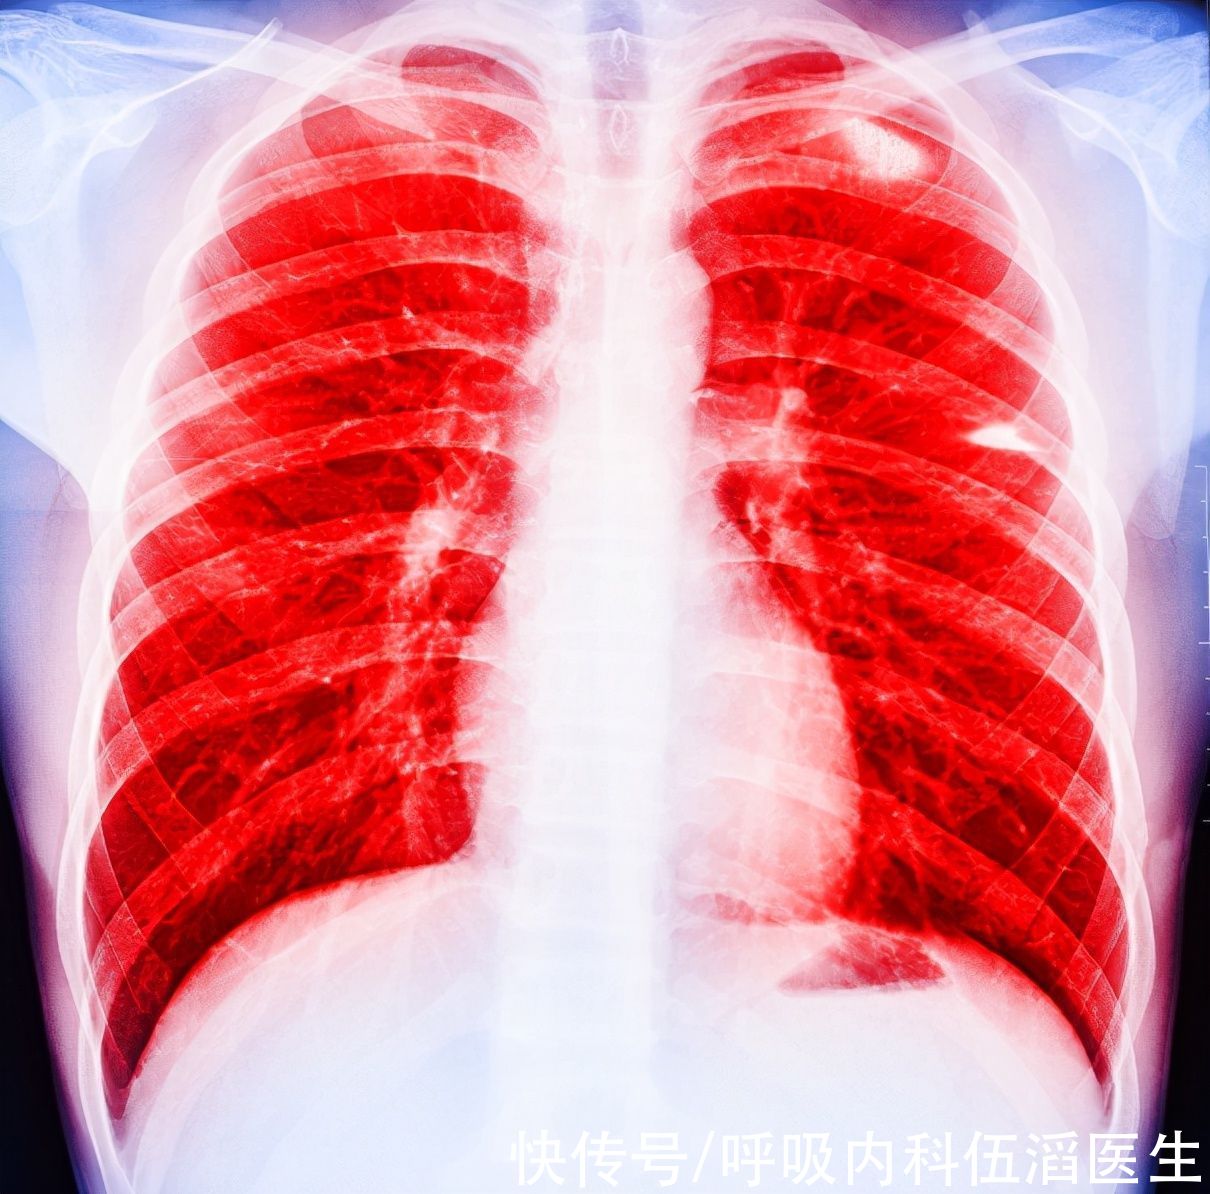

想要避免重蹈小吴的覆辙,该如何早点发现肺癌呢?记住下面这几种症状

1、出现持续性的干咳,这种情况在夜晚睡觉的时候最为明显,小吴母亲最初的症状就是如此。如果出现了这种症状,一定要引起重视,如果当你发现咳出的痰里发现了血丝的话,可能为时已晚了。

2、夜间失眠或者突然地惊醒,当人的肝脏和肺部出现了问题后,很容易就会将在夜间突然醒来,出现了这种情况,可能是肺在提醒你它出了问题。

3、睡觉时胸背部疼痛,癌细胞会压迫到周围组织,引起胸背部疼痛,这种疼痛在夜晚睡觉的时候会特别明显。

【 新药|肺癌来临,睡觉先知!医生有话说:肺部有癌的人,睡觉有这些表现】4、睡觉时出现呼吸不畅,多是肿瘤阻塞了气管导致的,身体躺下以后,这种情况会加剧,但是要注意的是,不是所有的睡觉时引起的呼吸困难都是肺癌,像心衰与肺水肿等都会导致呼吸困难。